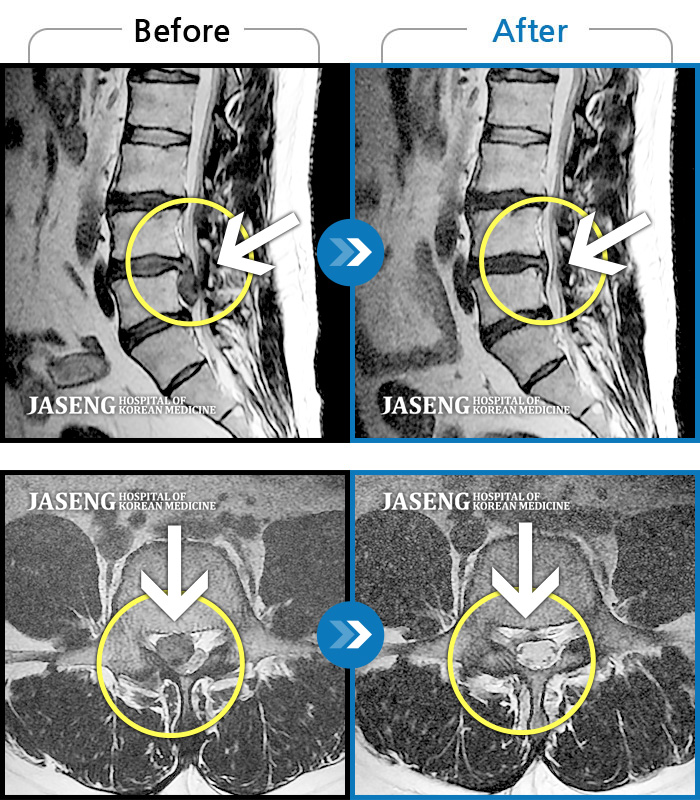

허리디스크

일산 · 김태용 원장

허리와 우측다리가 심하게 저렸다.

촬영시기

2020.05.07 ~ 2020.12.29

2021.02.26